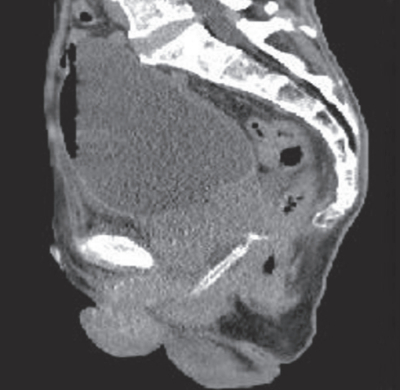

体温36.8℃、脈拍76/分。血圧120/80mmHg。呼吸数16/分。SpO2 98%(room air)。外尿道口からの出血を認め、尿道カテーテルに連結する蓄尿バッグ内に尿が出ていないことが判明した。腹部CT矢状断像と冠状断像を別に示す。